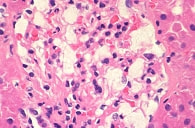

腎生検とは、超音波検査で腎臓の位置を確認しながら、からだの表面から腎臓に針を刺して組織を取り、採取した組織を顕微鏡で検査する方法です。この組織をみることによって、腎炎の程度や活動性の程度を知ることができます。この情報をもとにして、ステロイド薬の投与量を決めたり、あるいはステロイド治療の有効性を予知することができます。ただし、むくみがあったり、出血しやすい患者さんには腎生検は行いません。またこの検査は、患者さんに検査の必要性を説明し、文書で同意取得ができた場合にかぎって行います。